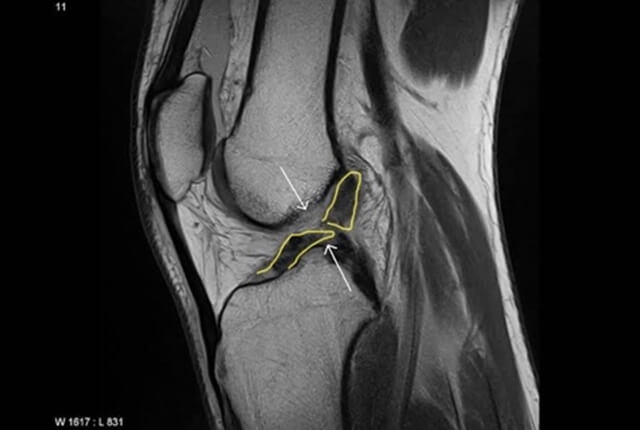

• MRIでACL損傷や半月板損傷を確定診断

診断1

診断2